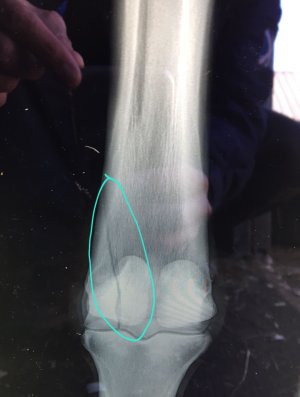

Abscess? Same number of teeth each side (I think) but a lot of swelling on one side?

Yup. Your horse was incredibly lucky. This one not so much. He had an abcess on his jaw under his cheekbone about 6 weeks prior to these xrays. It was lanced, drained and treated with antibiotics. All cleared up. Or so we thought. No more symptoms presented until some swelling appeared by their jaw and their mouth was bleeding. Nothing appeared obvious so we assumed they had bitten the inside of their mouth. Opened up in a gag and it showed a lot of problems hence the xrays.

The gap in the right hand side is a mass of infection that had eaten away at the bone. There was a very, very slim line of bone left. We could have dug out, scraped and cleaned the bone out before grafting some other bone onto it. But there was such a small amount of bone left that you couldn't guarantee that there was enough healthy bone left after scraping to graft to. Right up until the day of the blood in the mouth the horse had been working away and not presenting with any issues what so ever.

This horse did not come home 😢